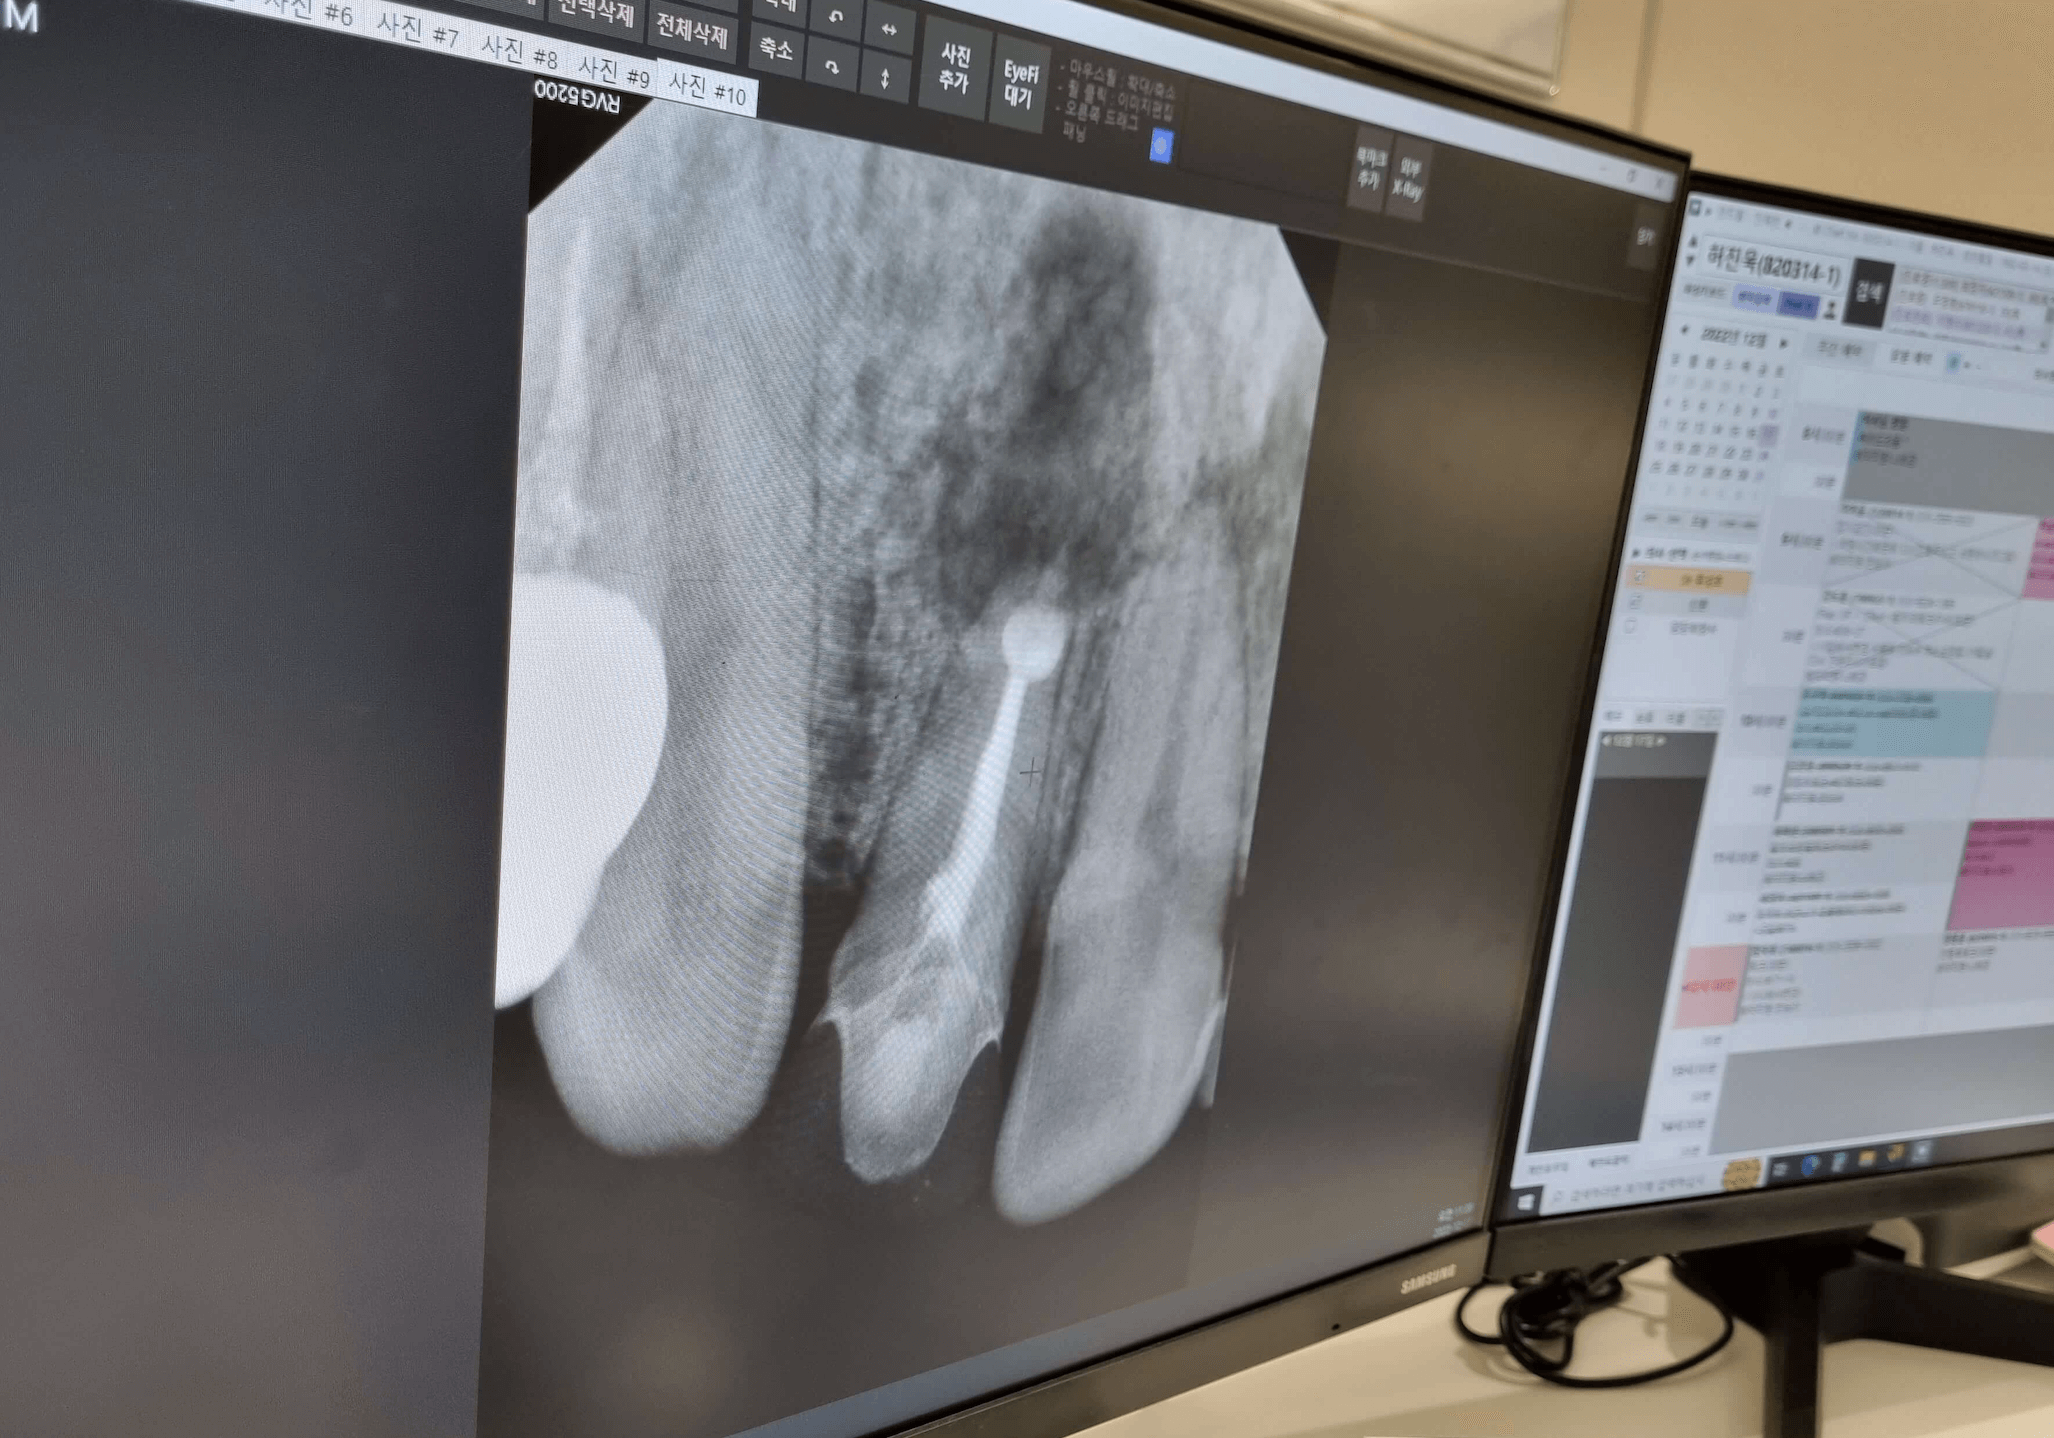

임플란트를 할 때 보다 임플란트 성공률을 높이기 위해 뼈가 부족한 경우 뼈이식을 함께 진행할 수 있습니다. 치과에 따라 뼈이식 비용이 30만원인 경우도 있지만 50만원까지 받는 치과도 있으니 사전에 뼈이식을 해야한다면 비용이 얼마나 들어가는지 물어보세요.

임플란트시 뼈이식을 하면 고정력이 높아져서 쉽게 흔들리거나 빠지는 경우를 사전에 예방할수 있으며, 음식을 씹을때도 뼈가 든든히 받쳐주어서 씹는 치아 힘이 상승 합니다. 뼈이식을 함께 병행하는 경우 임플란트 재수술 위험을 낮출수 있는 장점도 됩니다.